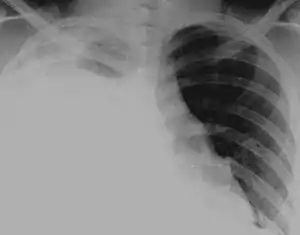

آبجنبی* یا هیدروتوراکس(به انگلیسی: Hydrothorax)* تراکم نابهنجار مایع آبگون (serous fluid) در حفرۀ جنب است. این وضعیت اغلب ثانویه به نارسایی احتقانی قلب، به دنبال افزایش فشار هیدرواستاتیک درون ریهها است. به ندرت، هیدروتوراکس میتواند در بیماران مبتلا به سیروز یا آسیت ایجاد شود. هیدرواتورکس کبدی، در مراحل پیشرفته و نهایی بیماری اغلب به درمان پاسخ نمیدهد. اگر مایع داخل حفره جنب چرکی باشد آن را پیوتوراکس، اگر خونی باشد هموتوراکس و اگر لنف باشد کیلوتوراکس مینامند.